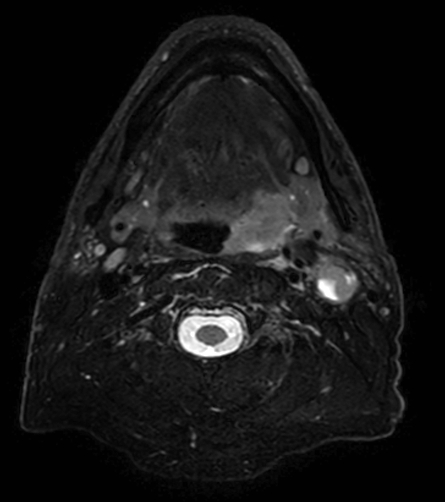

A 75-year-old male with oropharynx squamous cell carcinoma in the left tonsil region with extension into the soft palate, caudal border lower tonsil region, no midline crossing. On the left side in the neck there are also three enlared lymph nodes on level 2 and 3 with central necrosis and signs of limited extracapsular extensionn, T2N2b. Patient underwent MRI simulation in the radiotherapy (5-point) positioning mask in Ingenia MR-RT 3.0T using the Flex coils in combination with integrated Posterior FlexCoverage coil.

T2w TSE mDIXON (in-phase)